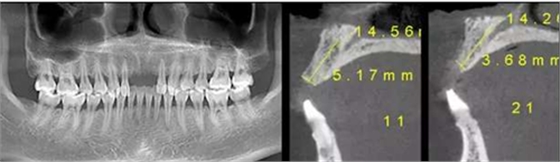

CBCT檢查顯示:水平向骨量不足,無(wú)明顯垂直向骨缺損。

2、針對(duì)骨量不足的問(wèn)題,種植體型號(hào)選擇3.5mm,同時(shí)進(jìn)行外科引導(dǎo)骨再生。

在11、21位置植入兩顆NobelActive 3.5mm*13mm種植體;